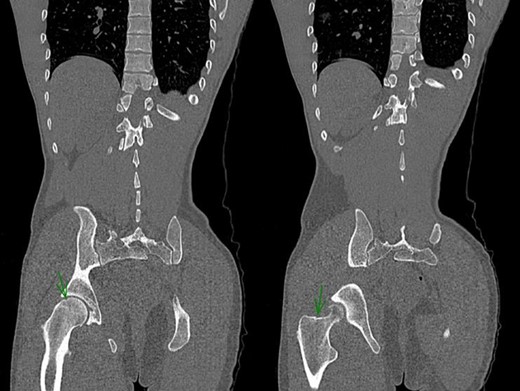

After reduction, the neurovascular examination remained normal. Pelvis CT-scan was performed and showed a bifocal fracture of the hip associating a non-displaced inter-trochanteric fracture and a non-displaced capital fracture (Fig. 2). Patient was discharged on day 5 with strict bed rest for 6 weeks.

Post-reduction CT-Scan of the pelvis showing a non-displaced fracture of the head of the femur and a non-displaced inter-trochanteric fracture of the right hip.